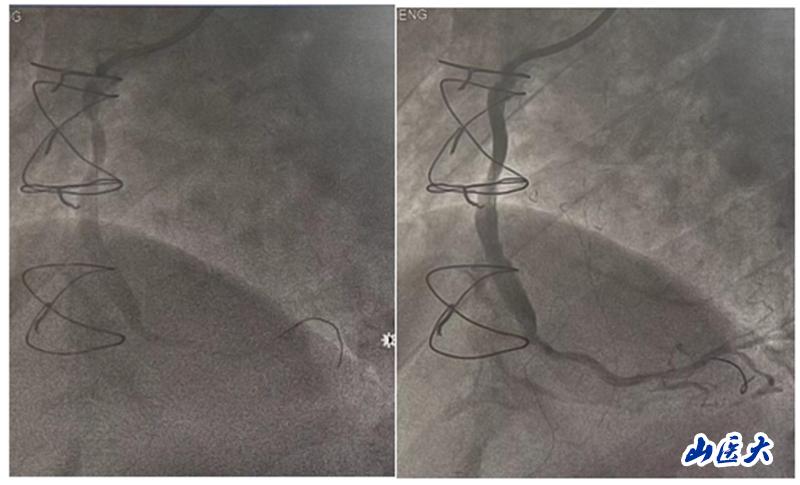

在手术中,团队发现患者的前降支、回旋支口部和右冠脉近段均存在闭塞情况,升主动脉-右冠脉桥血管近端狭窄约90%。团队决定对升主动脉-右冠脉桥血管进行介入治疗。他们快速准确地判断了病变血管的范围,并选择了激光消蚀辅助以及合适的球囊和支架进行干预治疗。手术后,患者安返病房,未再出现胸闷及气紧等不适症状。

据杨滨介绍,桥血管病变(SVG)在术后1年内出现闭塞的概率高达27%,而术后10年的闭塞率更是达到了50%。急性桥血管失败的主要原因通常是血流慢相关性血栓并发症,而晚期桥血管失败则往往与新生内膜增生和冠脉粥样硬化斑块进展有关。由于再次进行冠脉旁路移植术(CABG)风险极大,因此经皮冠脉介入治疗(PCI)已成为处理桥血管病变(SVG)的主要手段。

准分子激光冠脉消蚀技术主要通过光化学效应、光热效应和光机械效应三种原理达到治疗效果。它发出高能量脉冲,引起细胞的碳键断裂,释放的能量使细胞内水温升高,导致组织汽化并产生压力。通过组织的迅速膨胀和收缩,可以达到消蚀斑块物质、改善冠脉血流的效果。这一技术通过消蚀病变血管内斑块,达到改善冠脉血流的效果,特别适用于处理复杂性日益增加的冠状动脉介入手术。